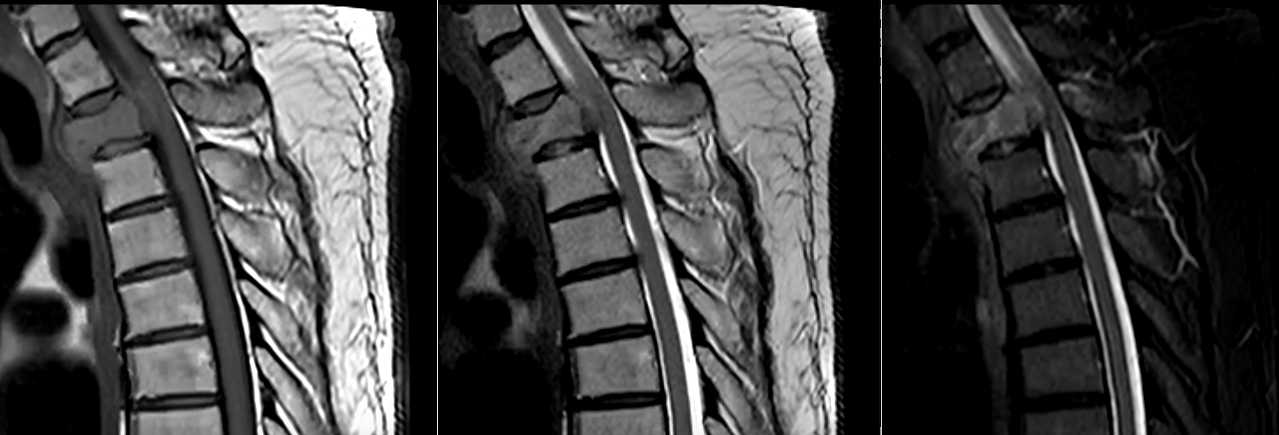

Diagnosticul tumorilor spinale osoase se bazează pe imagistică de înaltă performanță. Rezonanța magnetică este investigația principală, deoarece oferă informații detaliate despre os, măduvă și nervi. Tomografia computerizată este utilă pentru evaluarea distrugerii osoase.